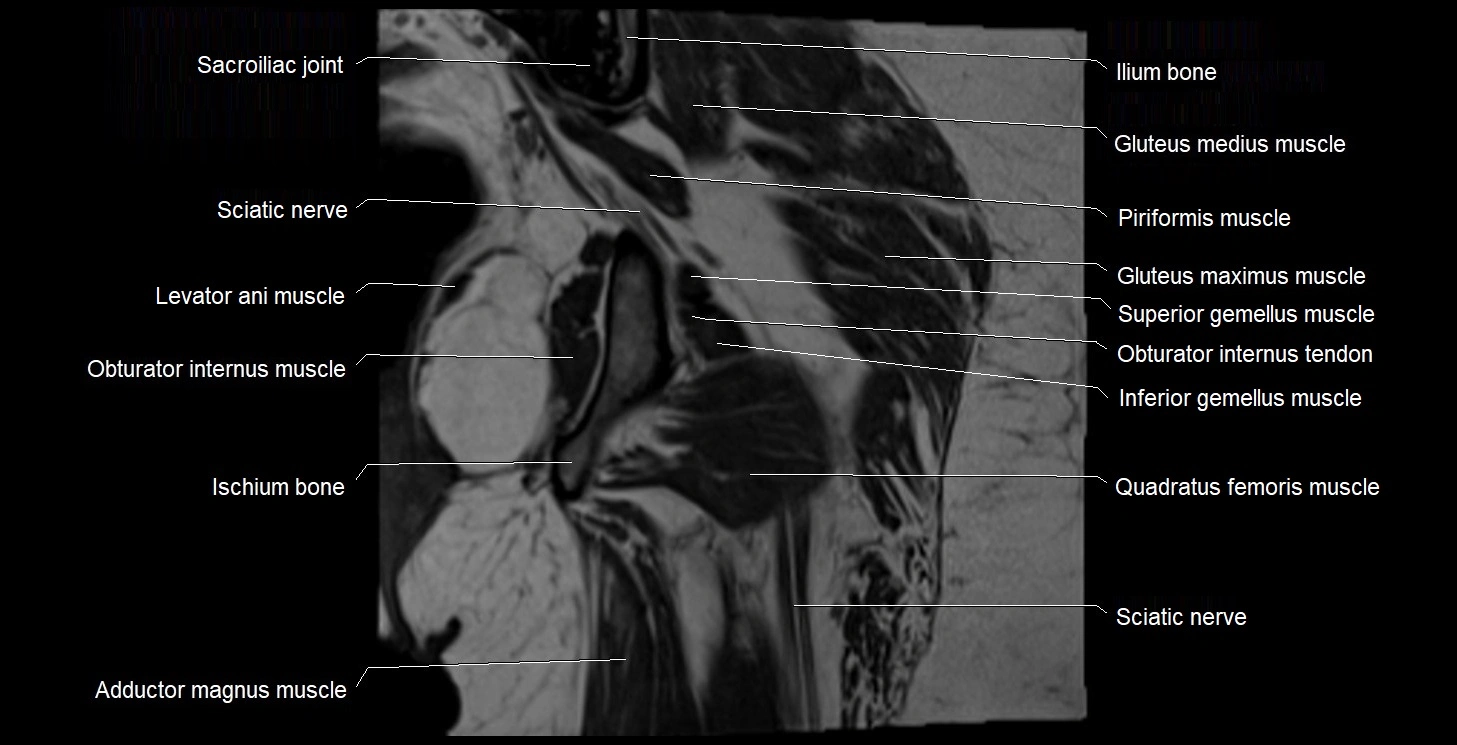

- Gluteus maximus muscle

- Gluteus medius muscle

- Gluteus minimus muscle

- Ilium bone

- Inferior gemellus muscle

- Ischium bone

- Levator ani muscle

- Obturator internus muscle

- Obturator internus tendon

- Quadratus femoris muscle

- Sacroiliac joint

- Superior gemellus muscle